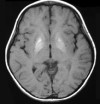

Энцефалопатия - причина ухудшения мыслительной деятельности

Однако более часто энцефалопатия формируется уже во взрослом периоде. Это может быть связано с патологией кровеносных сосудов, серьёзными черепно-мозговыми травмами, инфекционными заболеваниями головного мозга с органическими изменениями в тканях. Нередко энцефалопатия становится следствием отравления ядами, действующими целенаправленно на мозговые структуры, или развивается в результате развития опухолевого процесса, приводящего к сдавлению тех или иных участков мозга. Однако какова бы ни была основная причина, результат всегда один: головной мозг не получает достаточного количества кислорода, в мозговых клетках нарушается обмен веществ, накапливаются продукты обмена, что и приводит к постепенному ухудшению функций мозга, в том числе и высшей психической деятельности.

Среди всех вышеперечисленных причин возникновения энцефалопатий наибольший процент занимает сосудистая патология. Так, в результате засорения кровеносных магистралей атеросклеротическими отложениями, склерозных изменений в сосудистых стенках нормальный кровоток в этих сосудах нарушается. Постепенно из-за расстройства мозговой гемодинамики (т.е. кровотока) возникают мельчайшие очаги резкого кислородного голодания вплоть до инфаркта мозговой ткани. Фактически в этих очагах мозговая ткань просто-напросто отмирает, хотя из-за мелкомасштабности процесса внешне это проявляется лишь незначительно. Так, человека могут беспокоить головные боли, сонливость (или, наоборот, бессонница), повышенная утомляемость, агрессивность, раздражительность, снижение работоспособности. Такая симптоматическая картина свидетельствует о первой стадии развития мозговой патологии. Уже сейчас опытный специалист может обнаружить у пациента ухудшение интеллектуальных возможностей, особенно в таких областях, как память, внимание, способность сосредоточиться на одном предмете. Во второй стадии сосудистой энцефалопатии эти способности ухудшаются ещё больше, однако у пациента создаётся впечатление мнимого улучшения, поскольку вегетативные признаки (например, головные боли и др.) уменьшаются. Однако сам пациент всё же замечает, что память и внимание оставляют желать много лучшего. Наконец, в третьей стадии больной энцефалопатией не осознаёт даже этого, поскольку на данном этапе утрачивается возможность объективной оценки собственного состояния. Нередко вскоре после этого человек становится неспособным даже к элементарному самообслуживанию.